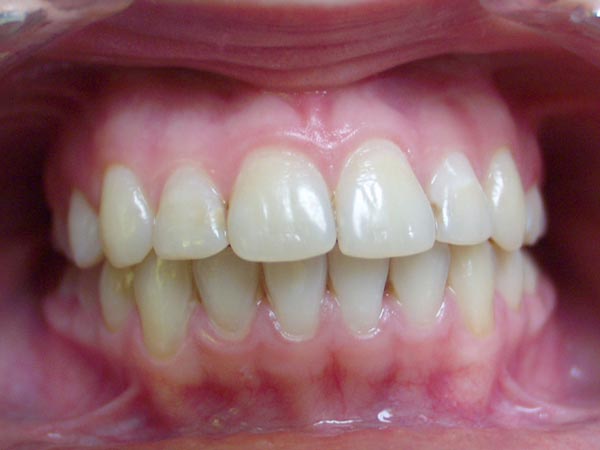

Фото 2. Пример правильно сформированного прикуса у ребенка.